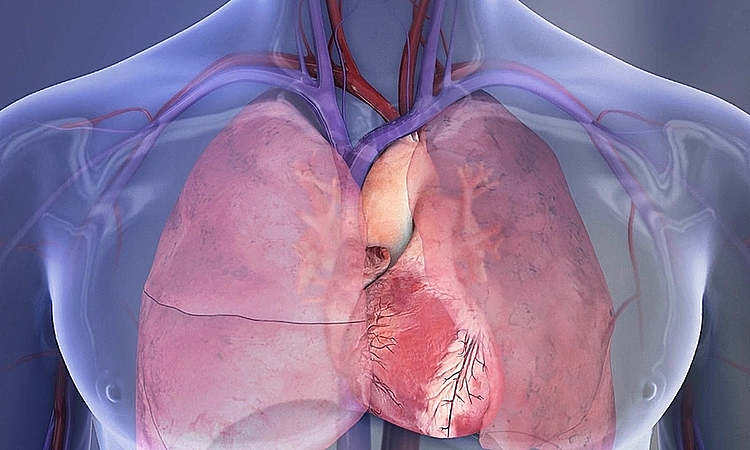

Ngay khi vào viện, bệnh nhân đột ngột ngừng tuần hoàn. Êkíp cấp cứu 115 phối hợp cùng bác sĩ hồi sức lập tức sốc điện, ép tim ngoài lồng ngực và hỗ trợ hô hấp, giúp tim ông đập trở lại. Kết quả chẩn đoán hình ảnh xác định bệnh nhân bị nhồi máu cơ tim cấp có biến chứng rung thất, tăng huyết áp, cần can thiệp mạch vành khẩn cấp.

Kết quả chụp mạch vành phát hiện một huyết khối lớn tắc hoàn toàn động mạch, thành mạch bị xơ vữa gây hẹp nặng. Trong lúc các bác sĩ thực hiện thủ thuật, trái tim bệnh nhân ngừng đập lần thứ ba. Một cuộc hội chẩn khẩn cấp tại chỗ giữa các chuyên gia tim mạch, hồi sức và gây mê được tiến hành. Họ phối hợp đồng thời nhiều kỹ thuật như ép tim, sốc điện khẩn trương mở thông mạch vành bị tắc.

Theo các chuyên gia, nhồi máu cơ tim xảy ra khi mảng xơ vữa trong động mạch vành nứt vỡ, tạo cục máu đông làm tắc nghẽn dòng máu nuôi tim. Tình trạng này dẫn đến hoại tử một phần cơ tim, gây rối loạn nhịp hoặc ngừng tim đột ngột, có thể tử vong nếu không can thiệp kịp thời.